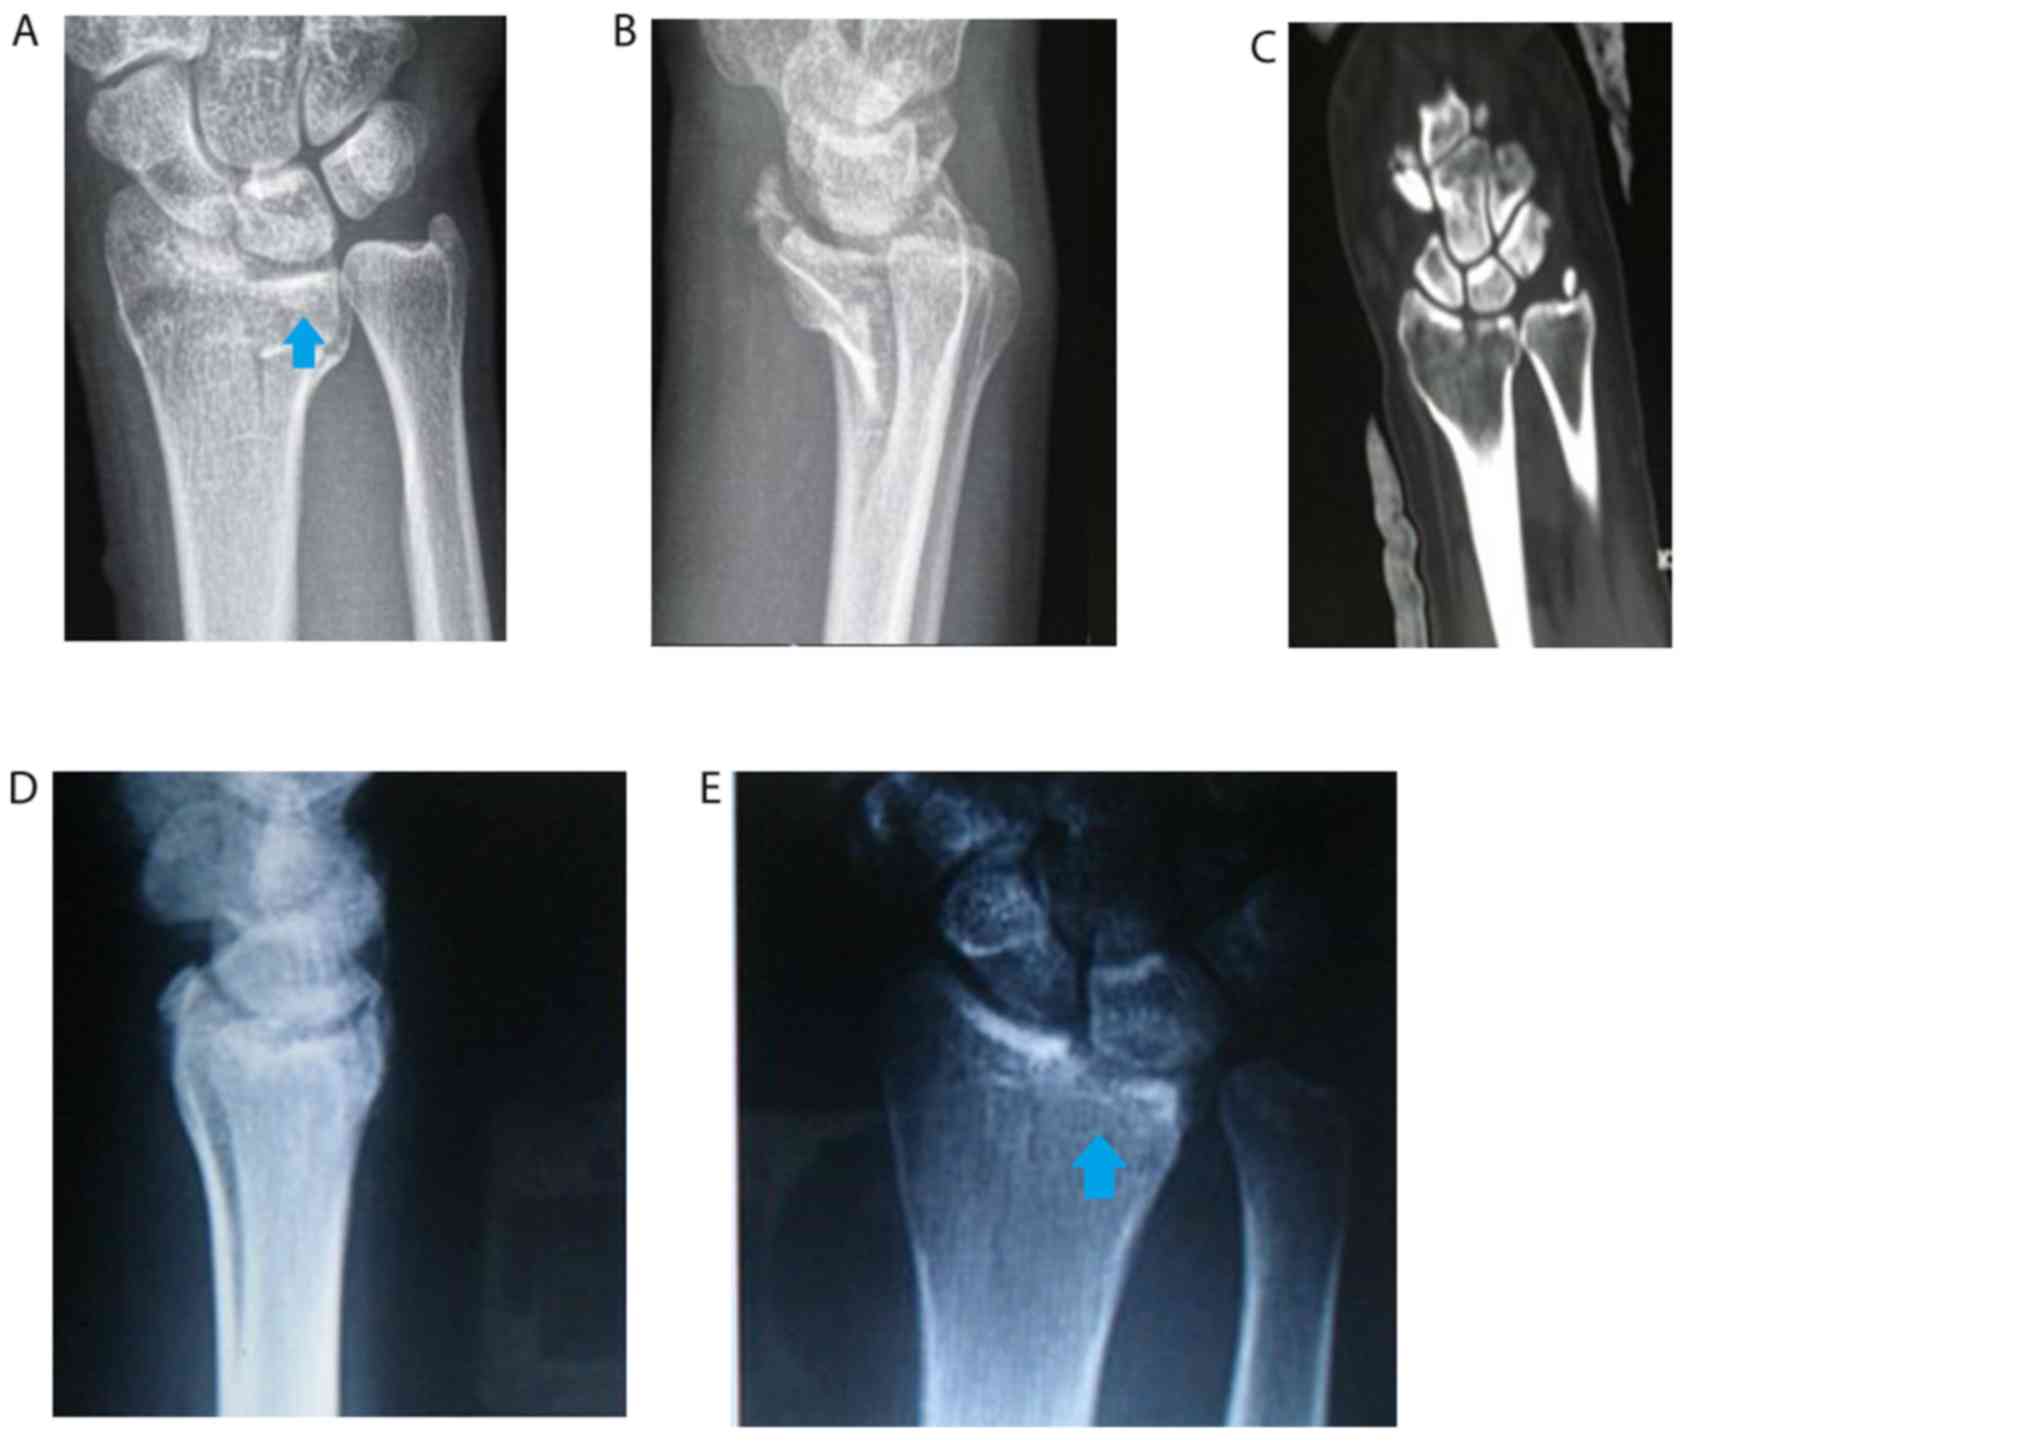

Figure 3.

Double-column die-punch fractures. (A) Sketch of double-column die-punch fracture (red area indicates fracture site). (B) Anteroposterior and (C) lateral radiographs and (D) 3D CT image of type I die-punch fractures. (E) Anteroposterior and (F) lateral radiographs and CT images in (G) 3D and in (H) sagittal and (I) horizontal planes of type II die-punch fractures. (J) Anteroposterior and (K) lateral radiographs and CT images in (L) 3D and in (M) coronal and (N) sigittal planes of type III die-punch fractures. (O) Anteroposterior and (P) lateral radiographs and CT images in (Q) 3D and in (R) coronal and (S) sigittal planes of type IV die-punch fractures. Arrows indicate the fracture site.

The type I and II fractures affected the articular surface of the radial column, without affecting the metaphysis of the radial column. Of note, no fracture was noted in the cortical bone at the radial side of the metaphysis. These factures were classified as type I with avulsion in the volar or dorsal edge of the middle column (Fig. 3B-D), and as type II for collapsed or comminuted fracture at the center or at the volar and dorsal sides of the middle column (Fig. 3E-I).

The type III fractures of the patients affected the metaphysis of the radial column, particularly the cortical bone at the radial side of the metaphysis, without affecting the articular surface of the radial column (Fig. 3J-N).

The type IV fractures affected the articular surface and metaphysis of the radial column. In addition, the fracture line of the radial column was usually horizontal and comminuted. Fig. 3O-S displays images of mixed-type fractures with fracture collapse of the middle column, and a combination of epiphyseal and articular fractures of the radial column.